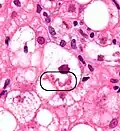

A small quantity of tissue is sampled from the liver when doing a biopsy, which is then examined under a microscope

Micrograph of non-alcoholic fatty liver disease, demonstrating marked steatosis (fat in liver cells appears white; connective tissue, blue). Trichrome stain

A liver biopsy (tissue examination) is the only test widely accepted (gold standard) as definitively diagnosing and distinguishing NAFLD (including NAFL and NASH) from other forms of liver disease and can be used to assess the severity of the inflammation and resultant fibrosis. However, since most people affected by NAFLD are likely to be asymptomatic, liver biopsy presents too high a risk for routine diagnosis, so other methods are preferred, such as liver ultrasonography or liver MRI. For young people, guidelines recommend liver ultrasonography, but biopsy remains the best evidence.[5][7][68][30] Liver biopsy is also the gold standard to detect hepatic fibrosis and assess its progression.[72] Routine liver function blood tests are not sensitive enough to detect MASLD, and biopsy is the only procedure that can reliably differentiate NAFL from NASH.[16]